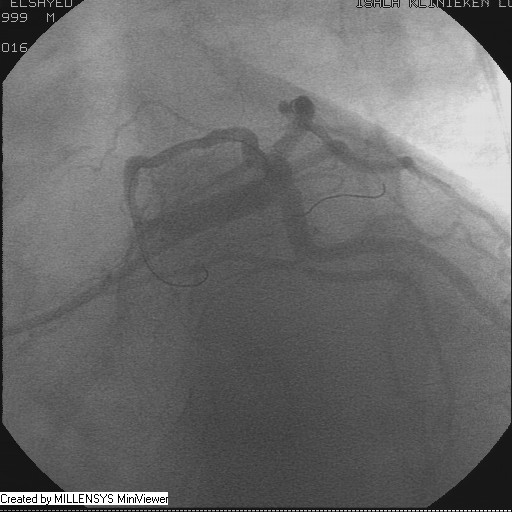

After crossing with the PTCA wire, a minimal flow started to appear in the diagonal branch (Figure 6), then LAD was wired, then a 2x15mm Balloon was used to pre-dilate (Figure 7,8), a big diagonal branch appeared with proximal thrombotic tight lesion (Figure 9), the diagonal angle to LAD was about 90 degree (Figure 10), so provisional stenting done to diagonal from its ostium with 3x20mm PROMUS ELEMENT PLUS DES (Figure 11,12), with good final result (Figures 13&14).

Figure 9